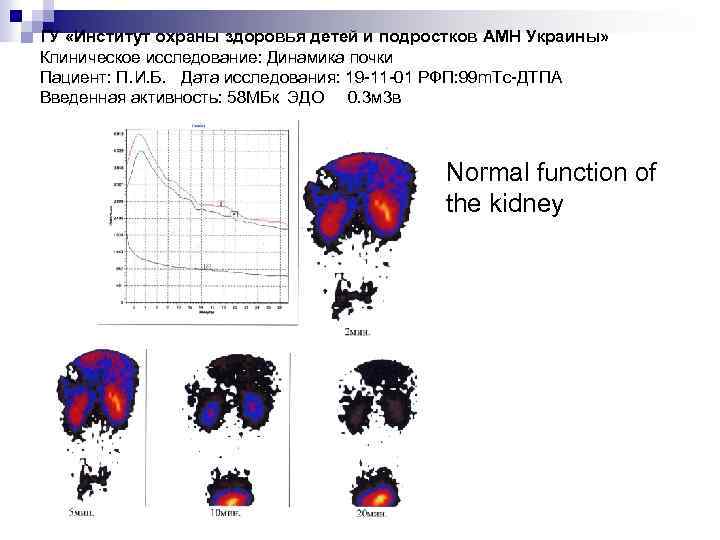

ГУ «Институт охраны здоровья детей и подростков АМН Украины» Клиническое исследование: Динамика почки Пациент: П. И. Б. Дата исследования: 19 -11 -01 РФП: 99 m. Тс-ДТПА Введенная активность: 58 МБк ЭДО 0. 3 м 3 в Normal function of the kidney

ГУ «Институт охраны здоровья детей и подростков АМН Украины» Клиническое исследование: Динамика почки Пациент: П. И. Б. Дата исследования: 19 -11 -01 РФП: 99 m. Тс-ДТПА Введенная активность: 58 МБк ЭДО 0. 3 м 3 в Normal function of the kidney